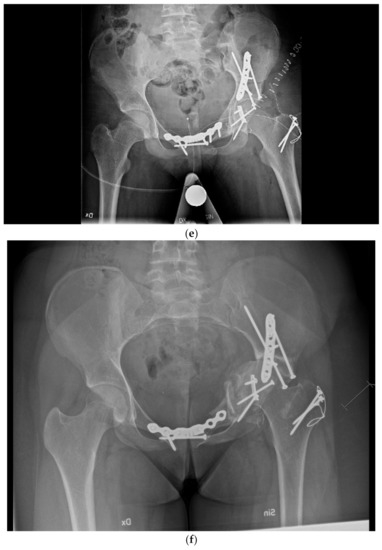

Figure 2.

Surgical failure of biological reconstruction after major pelvic surgery, salvaged with endoprosthesis. (a,b) A previously healthy 15-year old girl with 1-year history of left-sided groin pain. MRI of the pelvis (T1 TIRM coronal (a) and axial (b) images) showing a bone tumor involving the left superior ramus of the pubic bone and the periacetabular region of the iliac bone. There is a soft tissue component engaging the obturator internus-externus and adductor muscle. Staging procedures did not show any evidence of metastatic disease. Fine-needle aspiration showed a monotonous small round blue-cell tumor most likely representing Ewing sarcoma. FISH analysis showed an EWSR1-Fli1 fusion transcript confirming the Ewing sarcoma diagnosis. (c,d) After induction chemotherapy with VIDE (vincristine, ifosfamide, doxorubicin, and etoposide), the soft tissue component, as well as the intraosseous extension of the tumor, was significantly reduced, as shown on the coronal (c) and axial (d) T2 TSE FS MRI images. (e) The patient underwent a P2/P3 internal hemipelvectomy, extra-corporeal irradiation with 55 Grey and re-implantation of the autograft. (f,g) One year after primary surgery, the autograft collapsed (f), requiring salvage reconstruction with the Mutars Lumic Cup (g). A year later, the patient is functioning well and remains free of disease.